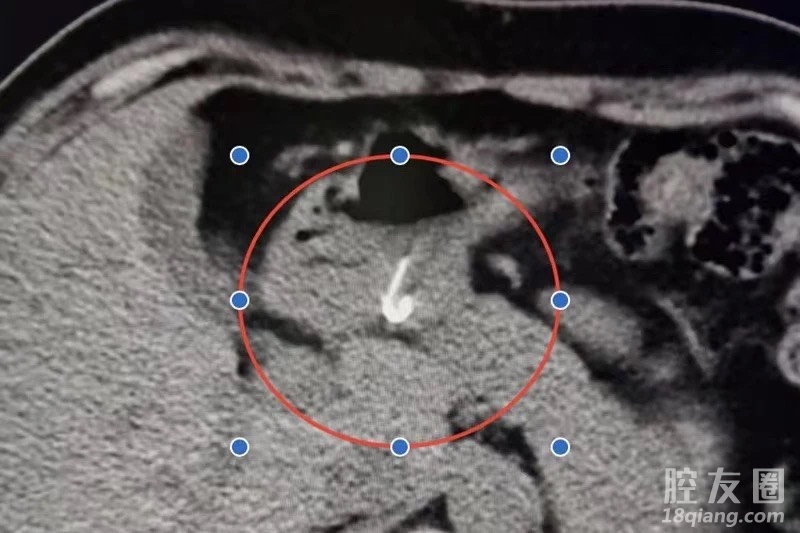

接诊后,医院急诊科主任胡国栋立即安排王先生做了腹部CT检查,影像检查显示其胃腔可见鱼钩样异物。经急诊内科、放射科、消化内科、内镜诊疗中心医生多科沟通会诊,并与王先生充分沟通后,决定对他进行消化道内镜下异物取出手术。

手术由陈云花操作,最终成功取出一枚长约2厘米的鱼钩。“所幸王先生在吃出第一枚鱼钩后不放心,及时到医院检查,不然后果不堪设想。”陈云花说,由于鱼钩等较锋利的异物进入消化道后极易引起消化道出血、穿孔等严重症状,必须争分夺秒进行治疗。